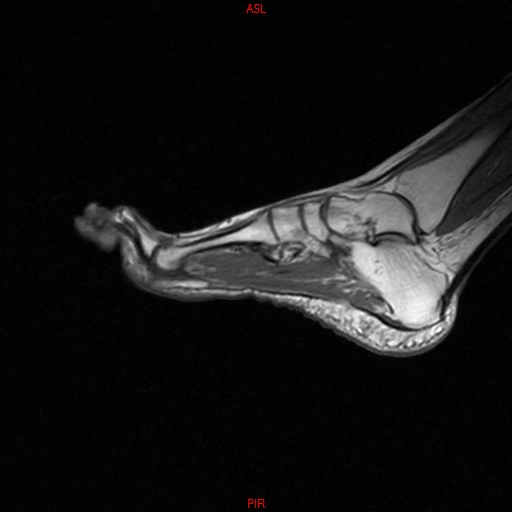

• RESONANCIA NORMAL TOBILLO SAGITAL T1

• RESONANCIA NORMAL PIE SAG T1